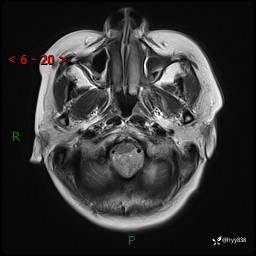

病例中年女性,头晕1年余。看看什么是软,什么是见缝钻---结果公布~

性别:女

年龄:47岁

简要病史:头晕1年余,间断恶心不伴呕吐

颅脑MRI平扫+DWI

轴内、轴外占位

轴内或轴外肿瘤